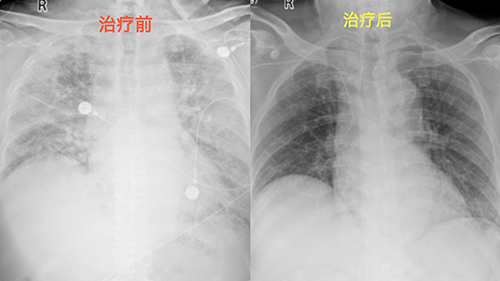

2026年2月5日,湖南省人民医院急诊ICU内一场紧急抢救牵动人心,28岁女子小丽因暴发性心肌炎陷入生命垂危境地,而她十指的长款美甲却在抢救关键期成为诊疗监测的阻碍,所幸医护人员联合专业美甲师及时化解难题,最终成功将小丽从死神手中夺回。这也为广大爱美人士敲响了健康警钟。